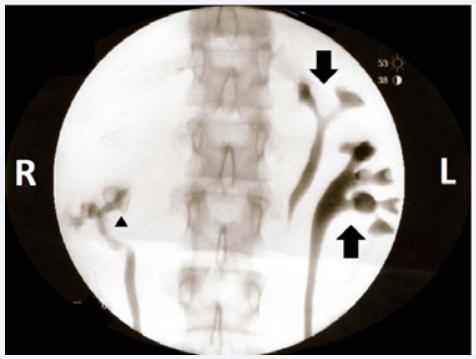

Figure 1 Fluoroscopic image of retrograde cystoscopy showing duplicated urinary collecting system of the left kidney. The upper pole moiety (downward arrow) and the lower pole moiety (upward arrow) can be observed on the side of the image labeled L. The lower pole moiety of the right collecting system is visualized as well (triangle).